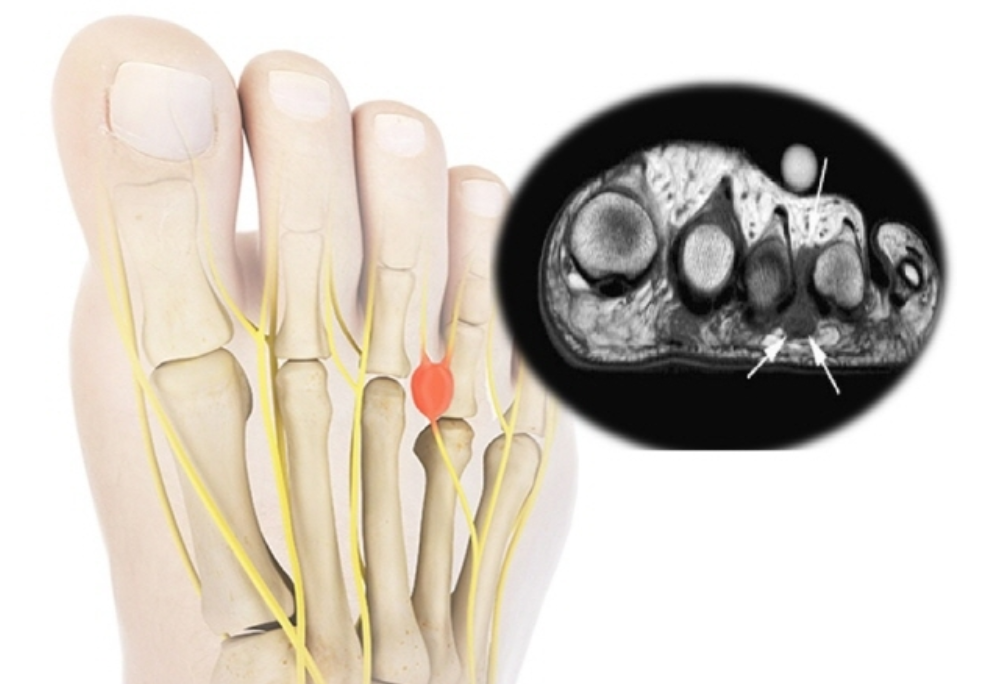

발바닥 앞쪽 ▶ 지간신경종

발바닥 앞쪽(발가락 쪽)에 통증이 지속된다면 지간신경종을 의심해야 한다고 합니다. 지간신경종은 발가락의 감각을 담당하는 신경이 과도하게 압력을 받거나 발가락 사이를 지나는 지간신경이 붓는 질환이라고 합니다. 대부분 둘째, 셋째, 넷째 발가락 사이에 생기는 것이 특징이라고 합니다. 지간신경종은 발볼이 좁은 신발 착용이 주원인이라 여성에서 많이 발생한다고 합니다. 발볼이 좁은 신발을 신으면, 지간 신경이 계속 압박을 받고 걷을 때 지속적으로 마찰을 입기 때문이라고 합니다. 지간신경종의 가장 흔한 증상은 걸을 때, 발바닥 앞쪽에 타는 듯하고 찌릿한 통증을 느끼며, 때로는 발가락의 저린 느낌이나 무감각이 동반되기도 하다고 합니다.

지간신경종 치료방법

초음파에 엑스레이로 지간신경종이 확인되면 발볼이 넓은 신발로 바꿔 신고 염증 주사 치료를 해야 한다고 합니다. 단, 통증이 심하고 신경종이 클 때는 수술로 제거해야 한다고 합니다.